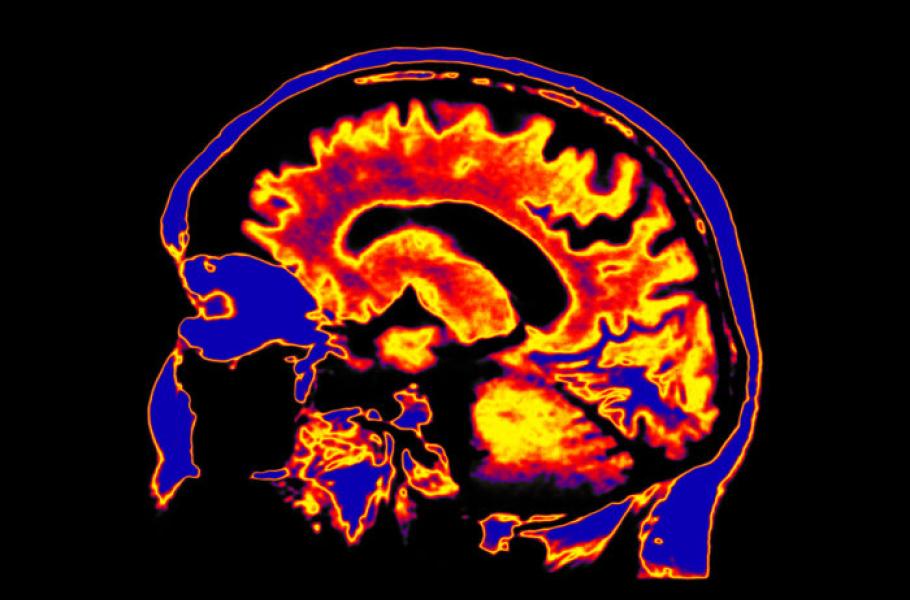

Výzkum v centru povede britský odborník Robin Carhart-Harris. Centrum se bude věnovat dvěma stěžejním směrů výzkumu: využití psychedelik v péči o duševní zdraví a léčby psychických poruch, a pak také studiu základů vědomí v lidském mozku. Cílem centra je také vybudování výzkumné kliniky. Tam budou vědci i lékaři získávat nové poznatky a testovat nové typy léčby s pomocí psychedelických látek. Tato klinika by se přitom měla stát prototypem pro podobná zařízení nabízející odbornou psychedelickou léčbu.